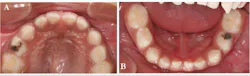

A three-year-old Hispanic male came to the clinic for his first dental visit. He was a well child without significant medical issues, and he regularly saw his pediatrician for well-child checks. The mother and patient denied any history of orofacial or dental symptoms, but mom was “concerned about a cavity in his bottom teeth.” The child was highly reactive to the dental environment and uncooperative for a knee-to-knee clinical exam. We were able to identify two carious lesions on the occlusal surfaces of the child's teeth—Nos. B and L (figure 1), but we were unable to obtain diagnostic radiographs.

Figure 1: Carious lesions noted on tooth No. B (shown in photo A) and tooth No. L (shown in photo B)